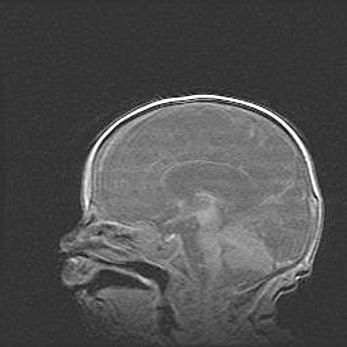

Множественные кисты обоих полушарий головного мозга, наибольшая из них в правой затылочной области. Ассиметричная атрофическая гидроцефалия.

Возраст: 7 месяцев

Вес: 5660 г

Пол: мужской

Окружность головы: 41,5 см

Срок гестации: 28-29 недель

Кисты головного мозга развиваются в результате многоочаговых некрозов вещества мозга и возникают вследствие перенесенной перинатальной инфекции, менингитов, энцефалитов, асфиксии, родовой травмы, расстройств мозгового кровообращения различного генеза. Образованию кист в веществе головного мозга плодов и новорожденных способствуют такие факторы, как высокое содержание в нем воды, недостаточная (или отсутствие) миелинизация и слабая астроглиальная реакция на повреждение.

Кисты могут сочетаться с гидроцефалией и другими поражениями головного мозга.